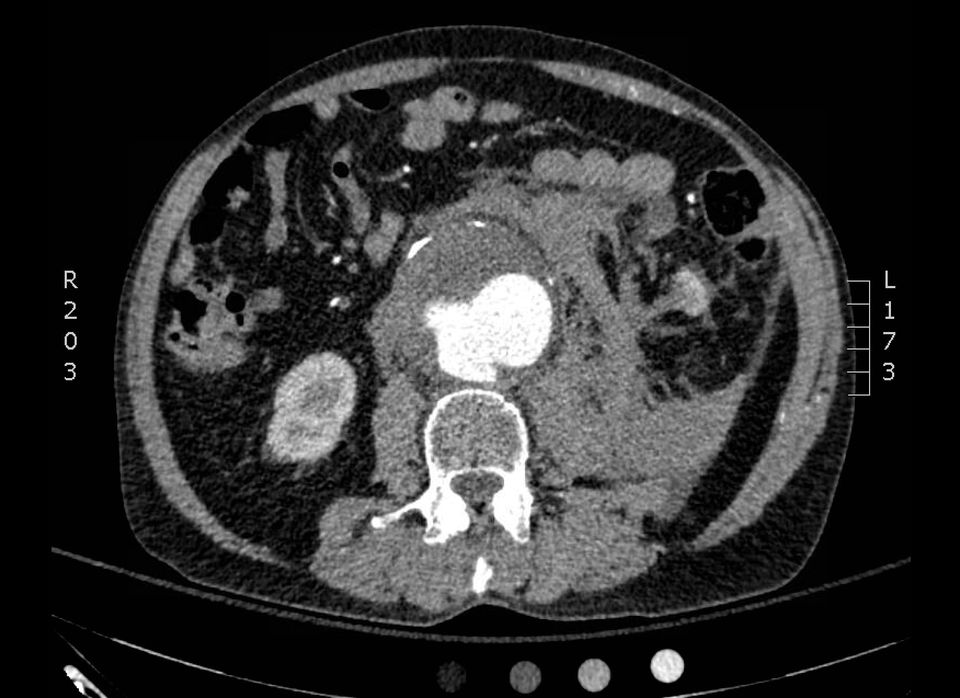

Short Case #3 for the Final FRCA